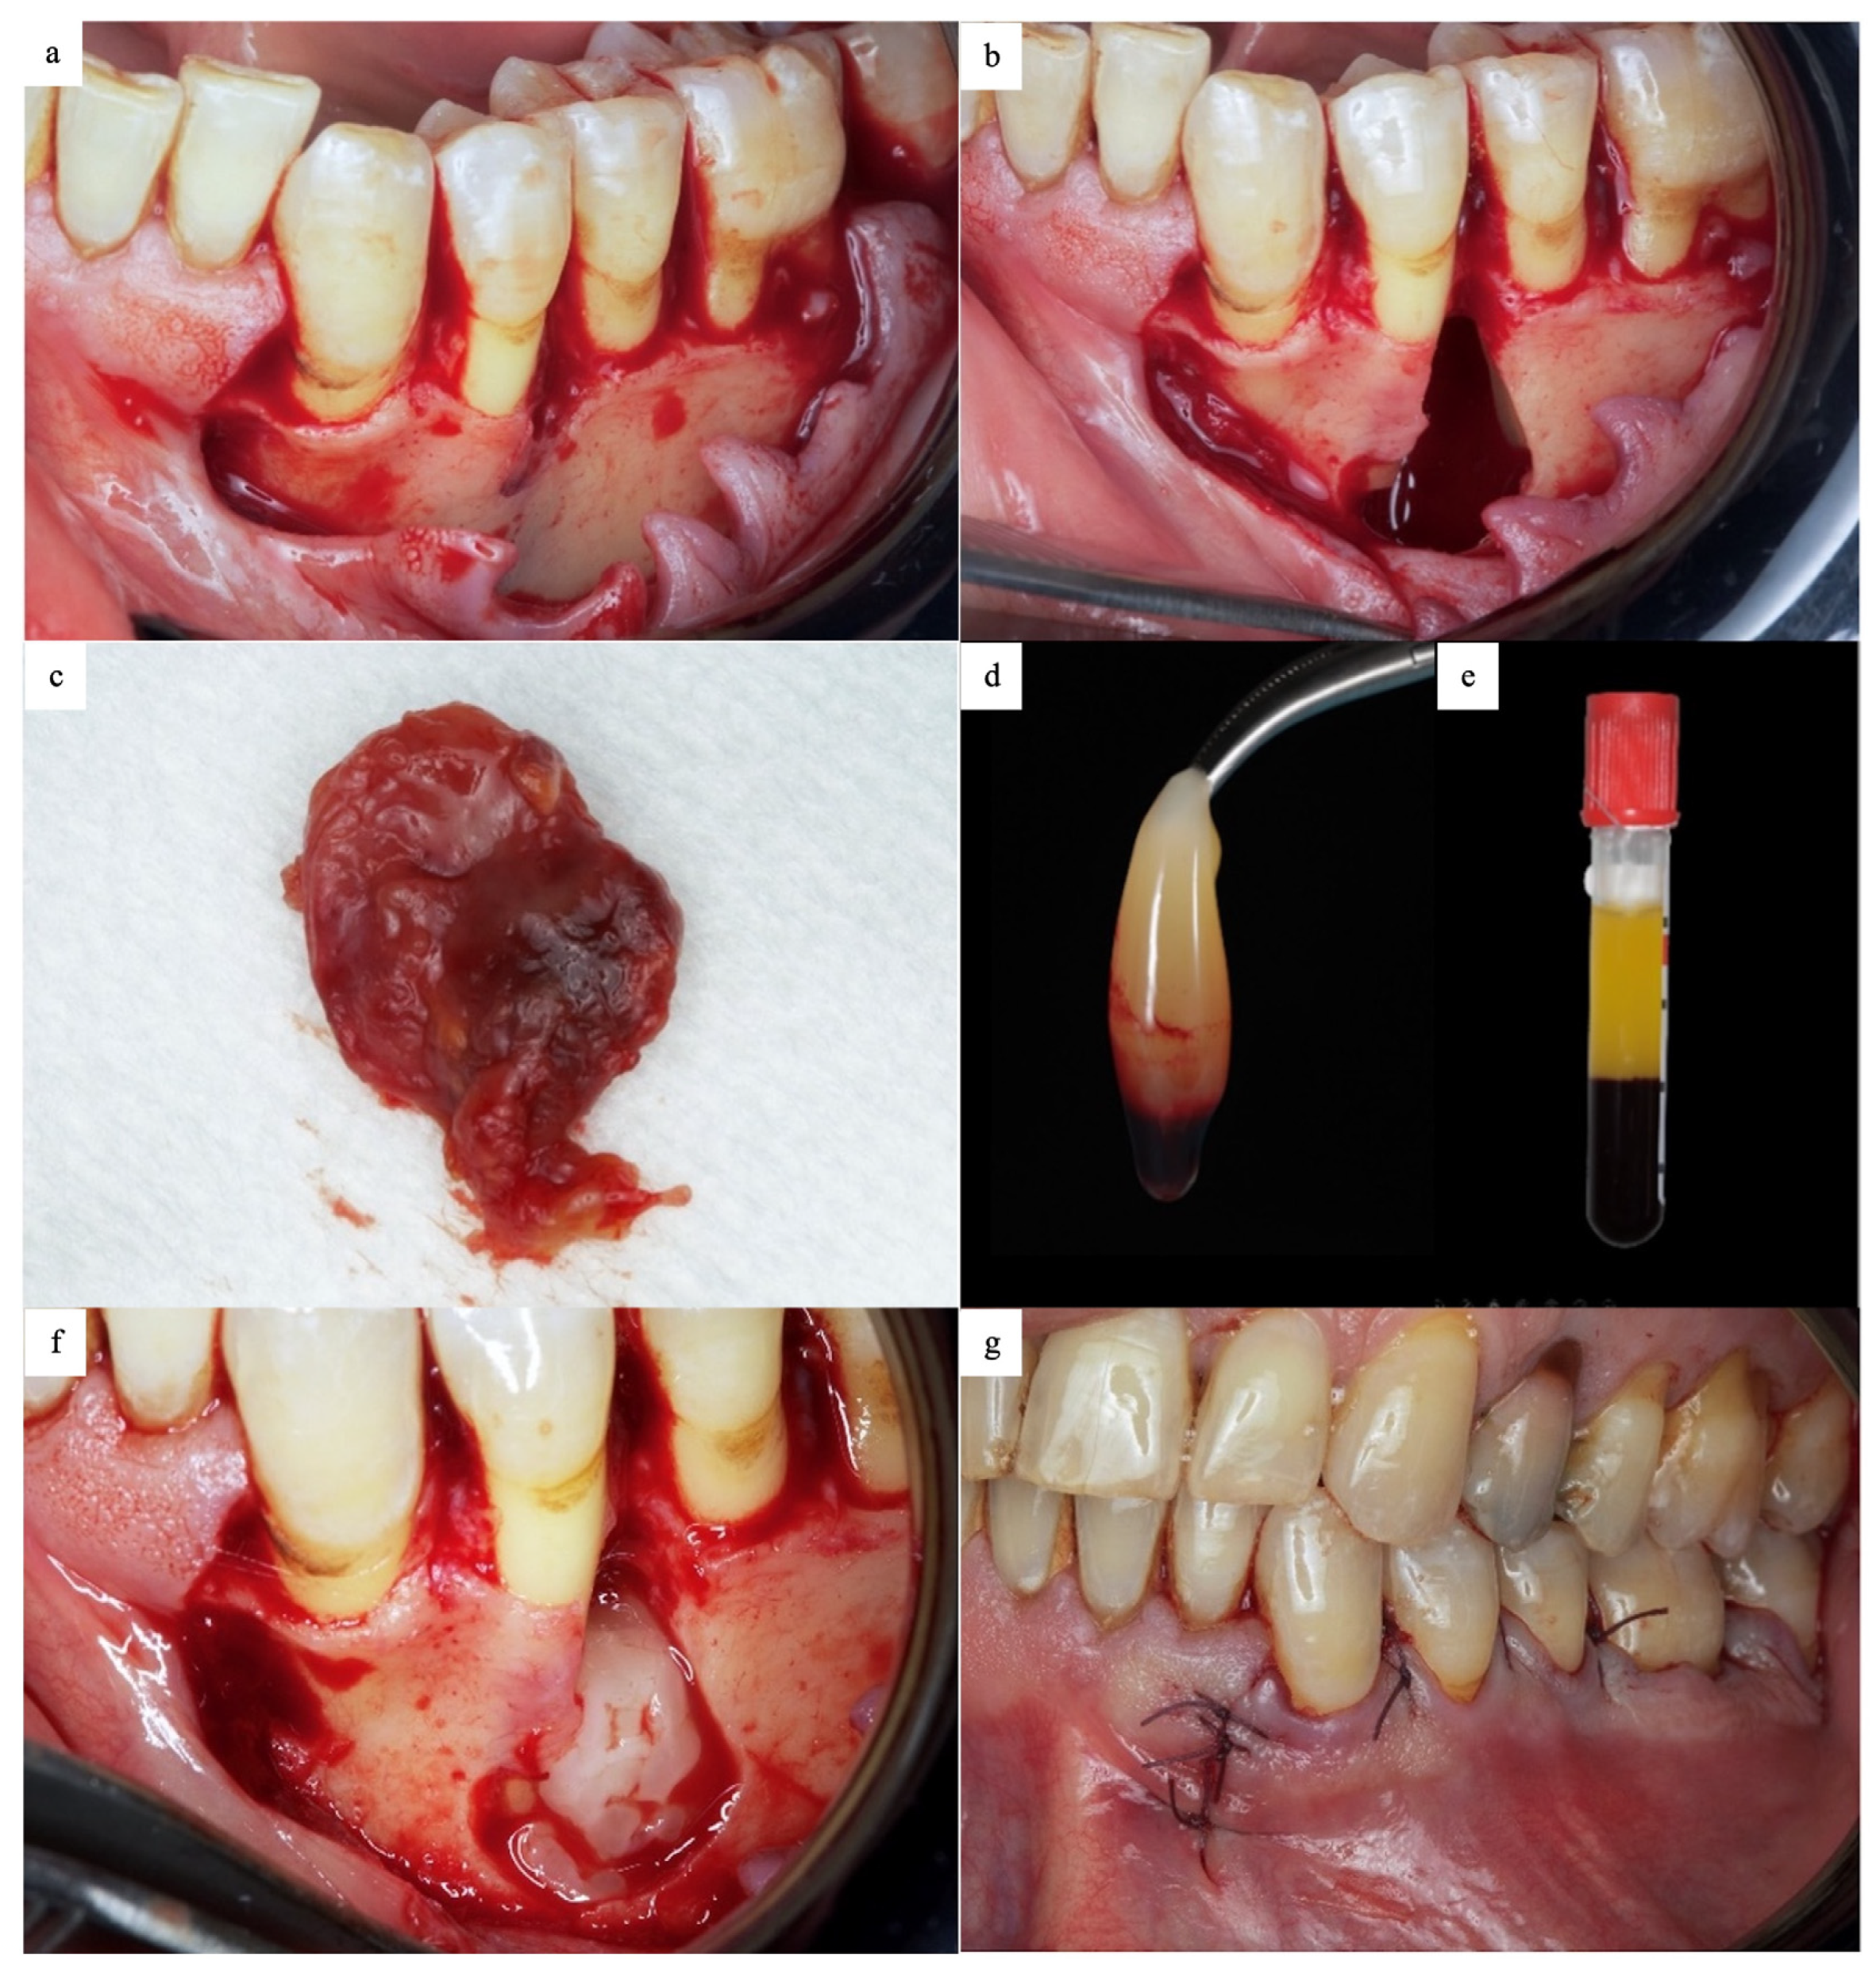

2.2. Surgical Phase

2.3. Postoperative Evaluation